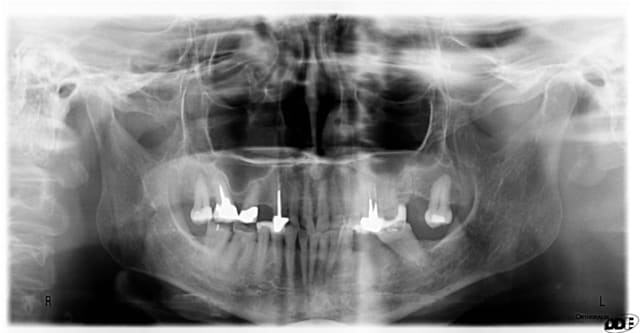

Cas similaire, mais sans érosion en pré-op, seulement attrition et perte de DVO. D'après moi, un patient bruxeur restera bruxeur....

après quelques traitements endodontiques, l'accord de la patiente pour couronnes en or complètes en postérieur; quasi indestructibles...et quelques implants pour les zones édentées..

Post op  2  y3limm - Eugenol

Post op  1  osgswu - Eugenol